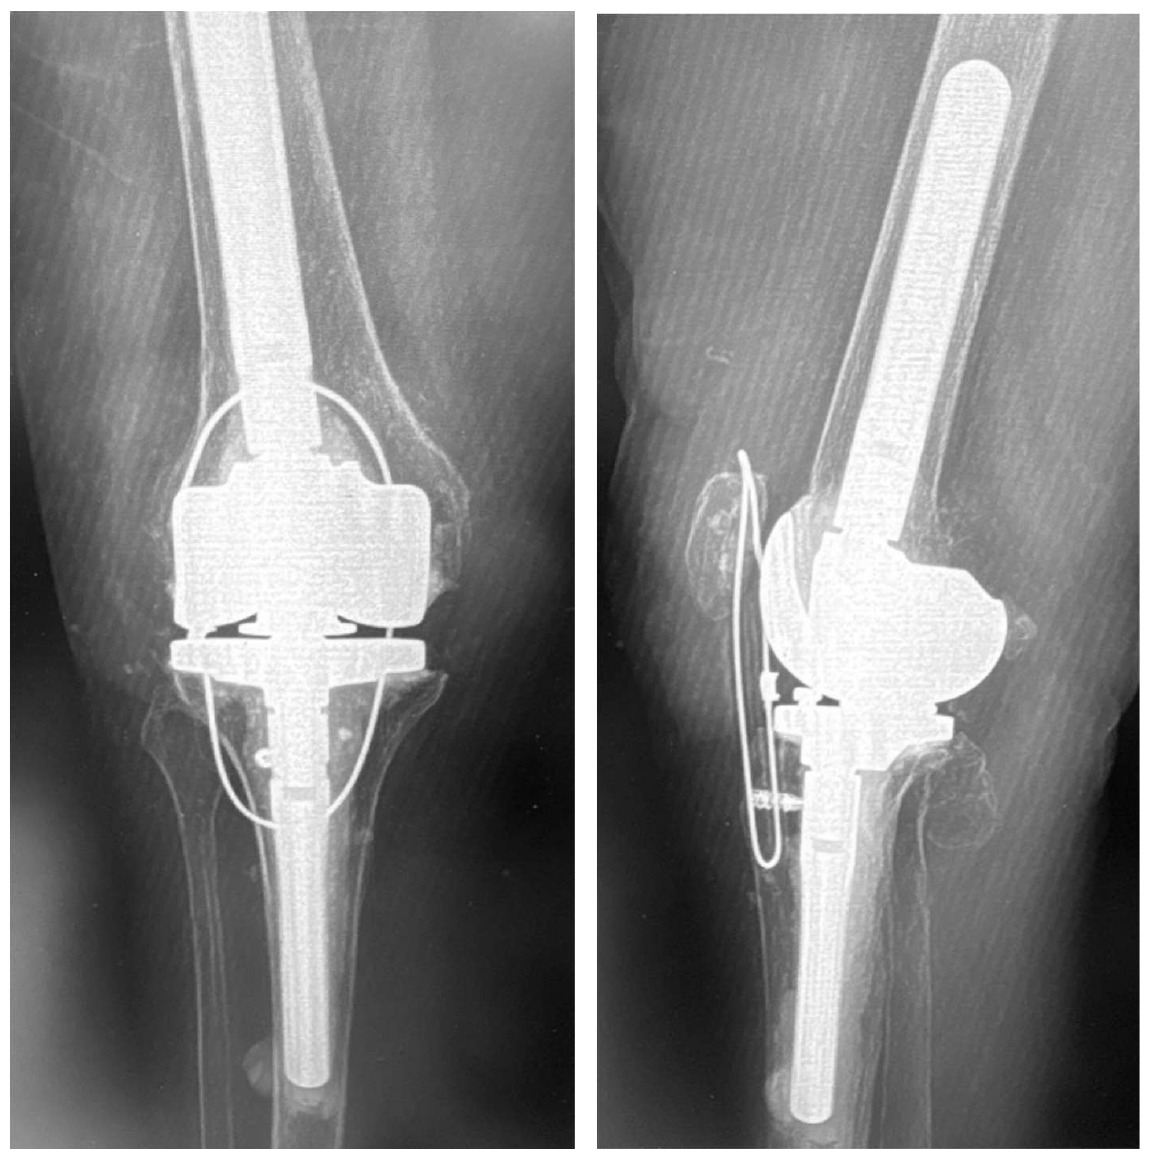

Following extensile exposure of the knee, an anchor suture is placed in the proximal tibia for the primary tendon repair. Next, a hole is drilled below the tibial tubercle through the diaphyseal bone, and the cable is passed through the tibia. Once passed through, the wire is laid within the gutters. (Figure 2) Before the cable is weaved through the quad, feel underneath to avoid passing the cable into the joint. (Figure 3) The cable is then weaved through the quad above the patella. (Figure 4) This technique allows for increased early tensile strength to that quad over time. Then, tighten and crimp the cable (Figures 5 & 6) and you bring the tendon together and then perform the repair. When tightening the cable

This is 74-year-old female, with a BMI of 33 kg/cm2, and multiple comorbidities (CHF, Arrhythmia, anxiety, 3 previous surgeries of the knee). She presented three months status post patellar tendon rupture, patellar fracture and dislocation. The patellar fracture was fixed with a wire, and in the radiograph you can see the anchor suture in the tibial tubercle area, the wire below the tubercle, within the gutters, and threaded above the patella. (Figure 8)

We removed the wire about six months following repair. At that time, she had ROM for 0-95 degrees. At six years out following repair she walks with no ambulatory aids and has full extension. (Figures 9, 10A-C)